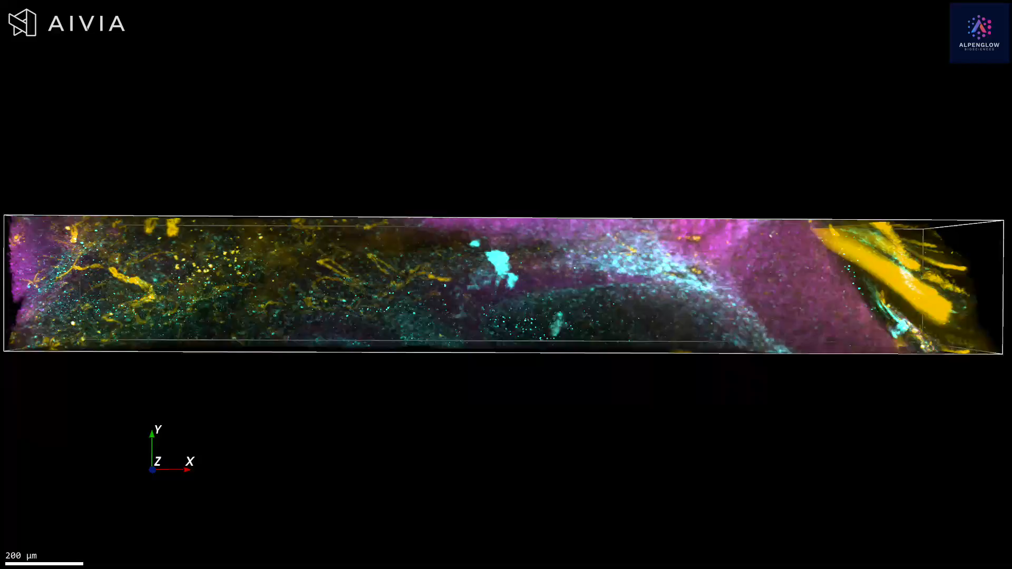

2 mm pig muscle section stained with CD31 and YO-PRO-1

2 mm pig muscle section stained with CD31 (green) for endothelial cells and YO-PRO-1 (red) for nuclei, revealing the intricate vascular network in extraordinary detail.

Using our Hybrid-Open-Top Light Sheet microscope, the 3Di, we seamlessly transition from fast, low-resolution overviews to high-resolution imaging of key regions. This unique approach delivers unparalleled speed and precision, uncovering insights impossible with 2D methods.